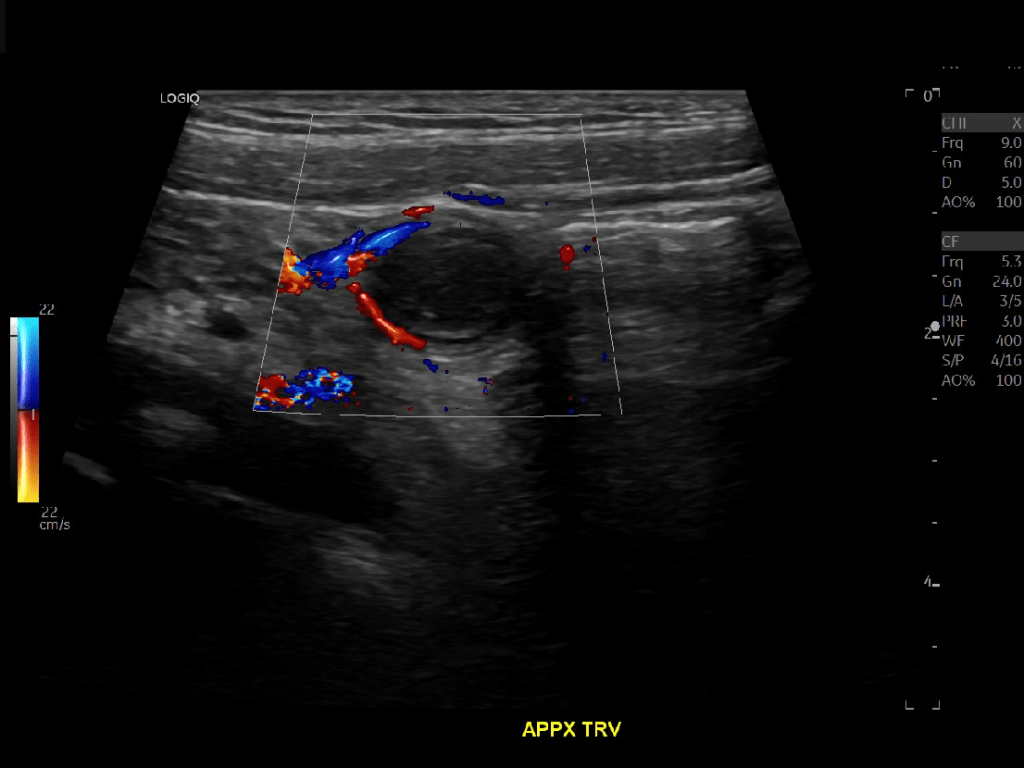

Appendicitis 13

Acute appendicitis @ 1 cm with L2-9mhz and L6-24mhz transducer GE Logiq e10.